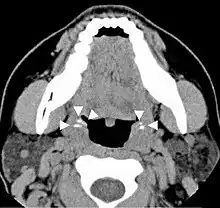

Imaging diagnostic techniques can identify a radiopaque mass that may be mistaken for foreign bodies, displaced teeth or calcified blood vessels. CT scan may reveal nonspecific calcified images in the tonsillar zone. The differential diagnosis must be established with acute and chronic tonsillitis, tonsillar hypertrophy, peritonsillar abscesses, foreign bodies, phlebolites, ectopic bone or cartilage, lymph nodes, granulomatous lesions or calcification of the stylohyoid ligament in the context of Eagle syndrome (elongated styloid process).[18]